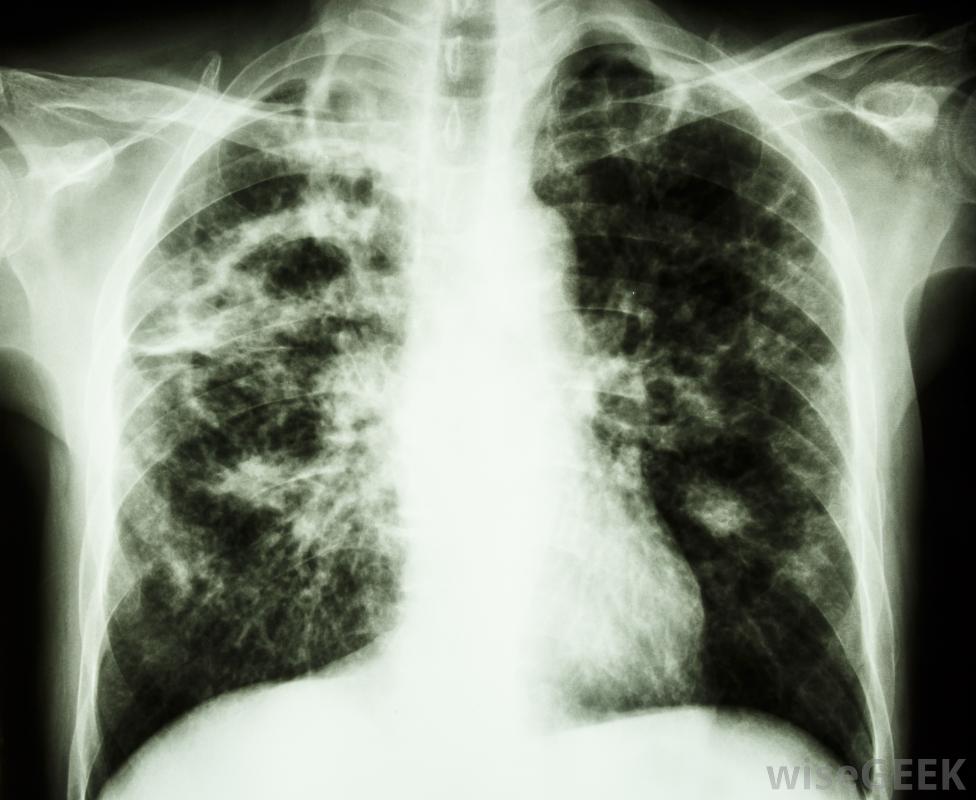

國王的邪惡是被稱為淋巴結腫大、淋巴結腫大或淋巴結腫大的疾病的另一個名字。淋巴結結核是結核性頸淋巴結炎的一個通稱,這種疾病是由頸部淋巴結結核感染的。在中世紀的法國和英國,人們認為這種病可以通過國王的撫摸來治愈,也就是所謂的皇室撫摸。為了治愈國王的邪惡,國王安排了特別的儀式,數百人被國王觸摸。在現代,國王已經被抗生素取代,成為治療的首選通常,肺結核會感染肺部,但在免疫系統較弱的患者中,它可能發生在淋巴結等部位。通常,肺結核感染肺部,但在免疫系統減弱的病人中,它有時會發生在肺外,比如淋巴結。國王的邪惡和淋巴結這個詞專門指的是影響頸部淋巴結的結核病,而不是身體其他部位的淋巴結。在幾乎所有的病例中,這種疾病成人是由結核分枝桿菌引起的。在所有的傳染病中,結核病是有記錄以來最古老的一種類型,人們認為自古以來就有國王的邪惡影響著人們結核病通常在肺部生存和繁衍,盡管它可能傳播到其他區域,如淋巴結英國的懺悔者愛德華和法國的菲利浦一世是第一批觸摸貪腐病人的國王,據說是為了治愈國王的罪惡。參加儀式接受王室撫摸的人會得到金幣,人們普遍認為它具有神奇的力量。一旦國王的邪惡病人開始使用皇室觸摸術,后來的國王就被認為繼承了這種特殊能力。肺結核的癥狀可能包括疲勞和咳嗽。一些君主觸碰了許多受國王邪惡折磨的人。據認為,路易十五可能接觸了超過2個,1825年,查理十世是法國國王中最后一個實行這種做法的國王。英國國王中最后一個對他們貪婪的臣民施以皇室色彩的人實際上是一位女王,安妮女王,她的統治一直持續到1714年X光片可以用來診斷肺結核,人們認為治愈國王邪惡所需的力量已經轉移到被國王觸摸過的硬幣上。這種情況發生在14世紀,硬幣被稱為天使。即使天使停止生產,人們也相信觸摸一枚外觀相似的金質獎章也會有同樣的神奇效果更現代的治療方法通常包括服用幾種不同的抗生素長達一年為了治愈國王的邪惡,那些參加儀式的人會得到金幣。